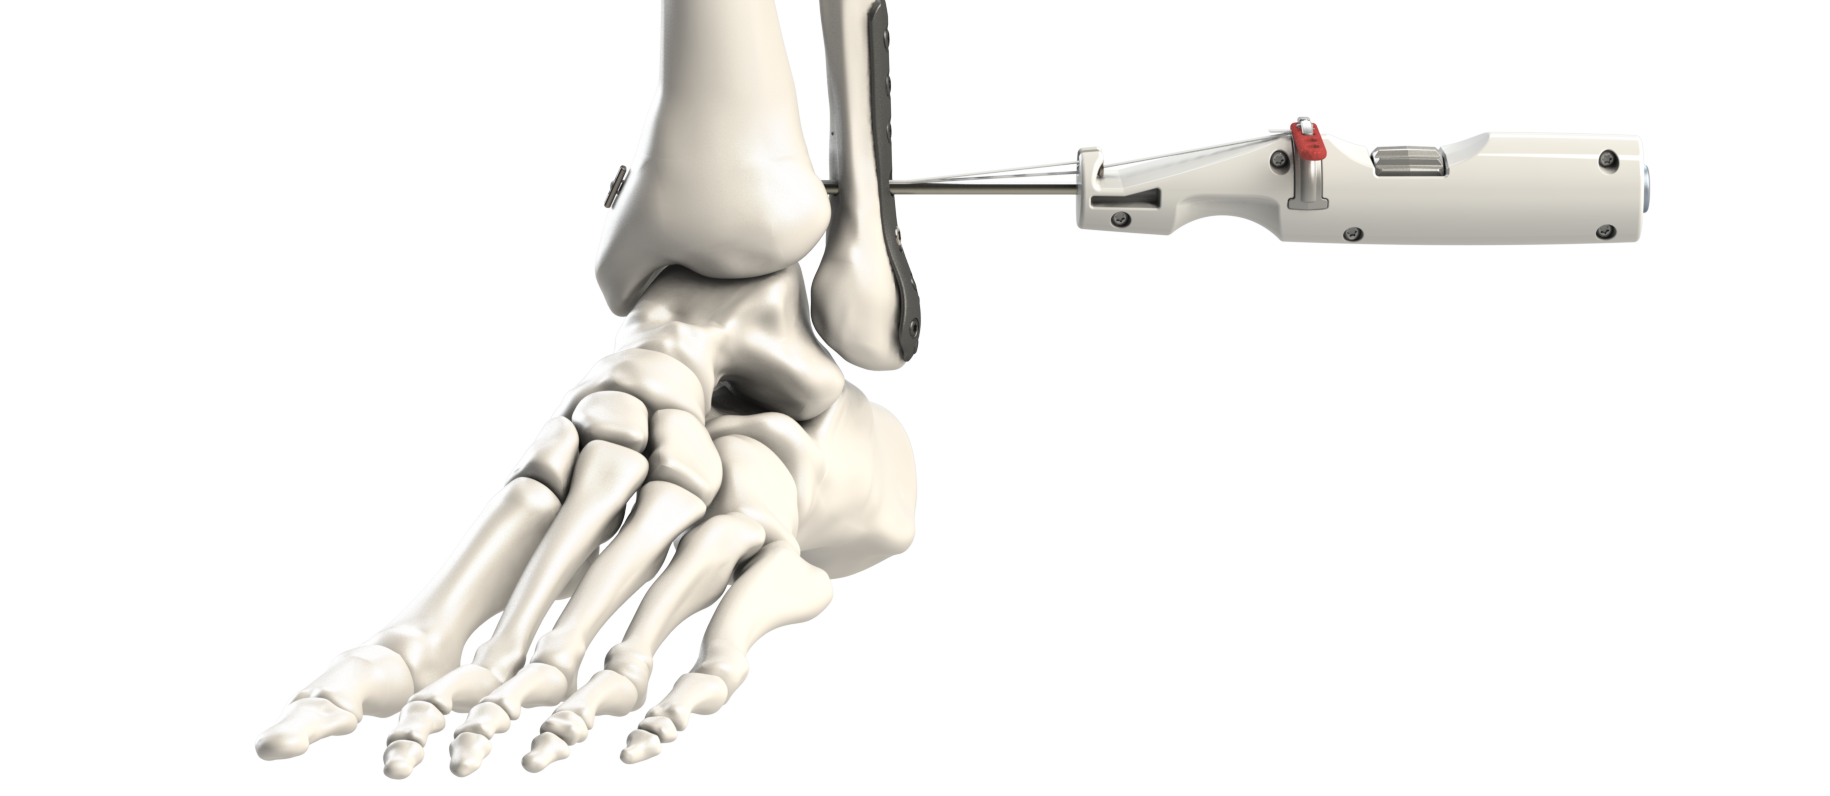

All

Ankle

Cannulated Screws

External Fixation

External Fixation

External Fixation